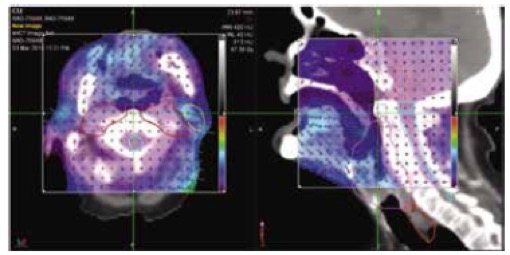

I. Delivery Analysis

Το σύστημα Delivery Analysis επεξεργάζεται με τρόπο αυτόματο τα δεδομένα από την εκτέλεση της θεραπείας κάθε ασθενούς και ελέγχει αν κάθε συνεδρία αποδίδεται όπως έχει σχεδιαστεί.

- Για κάθε ασθενή, το Delivery Analysis ελέγχει τη σωστή λειτουργία του κατεθυντήρα πολλαπλών φύλλων χρησιμοποιώντας το σήμα του ενσωματωμένου ανιχνευτή του συστήματος TomoTherapy. Σε περίπτωση εμφάνισης διαφορών το σύστημα αυτόματα υπολογίζει την επίδραση τους στην κατανομή της χορηγούμενη δόσης και ειδοποιεί τον ακτινοφυσικό και τον ιατρό.

- Σε κάθε συνεδρία το σύστημα μετράει και επεξεργάζεται την ροή φωτονίων στην έξοδο του ασθενούς (exit fluence) για να εξασφαλίσει την σωστή εκτέλεση της θεραπείας από την πρώτη έως την τελευταία συνεδρία.

Δοσιμετρικός έλεγχος πριν την εκτέλεση της θεραπείας

Το σύστημα Delivery Analysis παρέχει τα απαραίτητα εργαλεία για τον ποιοτικό έλεγχο των πλάνων θεραπείας κάθε ασθενούς. Συγκεκριμένα:

Το σύστημα Delivery Analysis παρέχει τα απαραίτητα εργαλεία για τον ποιοτικό έλεγχο των πλάνων θεραπείας κάθε ασθενούς. Συγκεκριμένα:

- πριν την έναρξη της θεραπείας εκτελείται μια διαδικασία δοσιμετρικού ποιοτικού ελέγχου,

- το σύστημα Delivery Analysis συλλέγει τα δεδομένα από τον ενσωματωμένο ανιχνευτή του συστήματος και

- ανακατασκευάζει την μετρούμενη κατανομή δόσης στις εικόνες αξονικής τομογραφίας του ασθενή και την συγκρίνει με αυτή του πλάνου θεραπείας

Ποιοτικός έλεγχος της ακρίβειας χορήγησης της θεραπείας

- Κατά την διάρκεια εκτέλεσης κάθε συνεδρίας και για κάθε ασθενή το σύστημα Delivery Analysis μετράει αυτόματα με τον ενσωματωμένο ανιχνευτή την ροή των φωτονίων στην έξοδο του ασθενούς

- Το σύστημα Delivery Analysis αναλύει και επεξεργάζεται αυτόματα την ροή των φωτονίων στην εξόδου του ασθενούς ώστε να εξασφαλίσει την σωστή εκτέλεση κάθε συνεδρίας της θεραπευτικής αγωγής του κάθε ασθενούς.